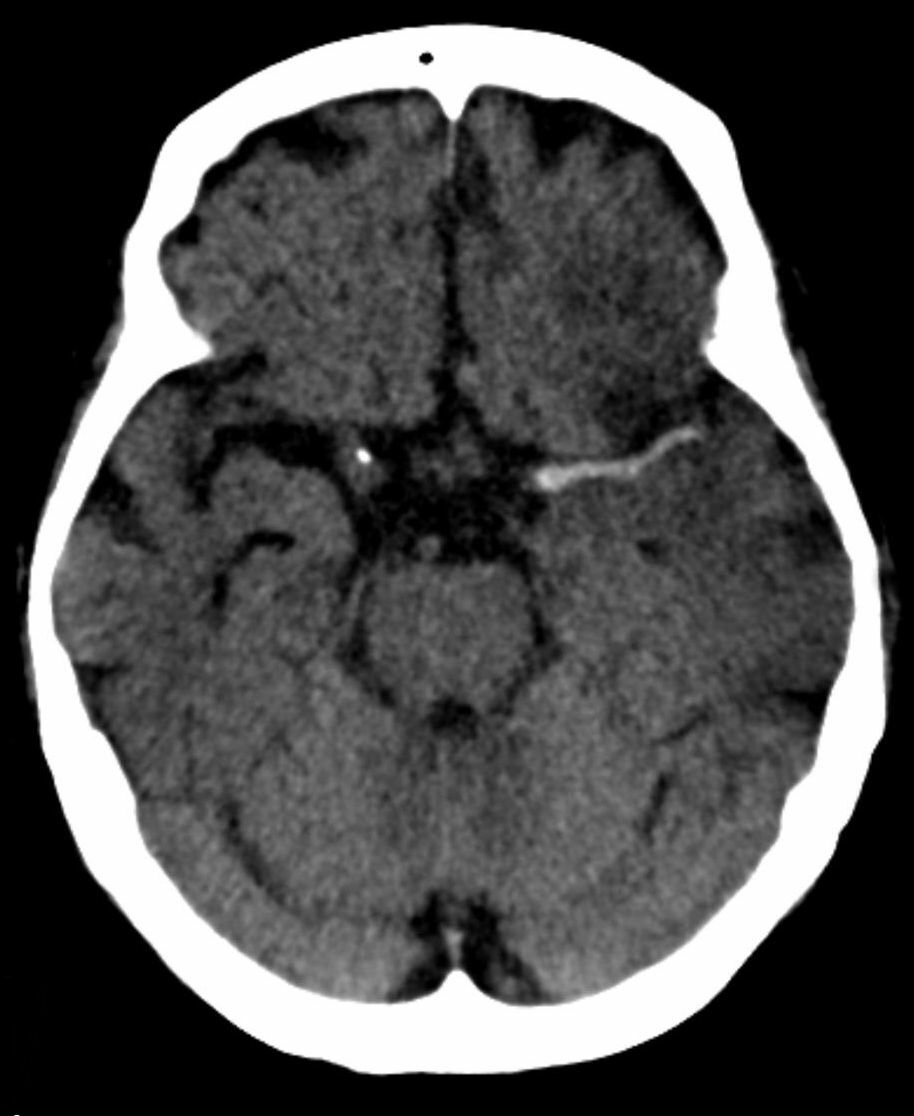

what does this CT head show?

A

hyperdense left middle cerebral artery thrombus